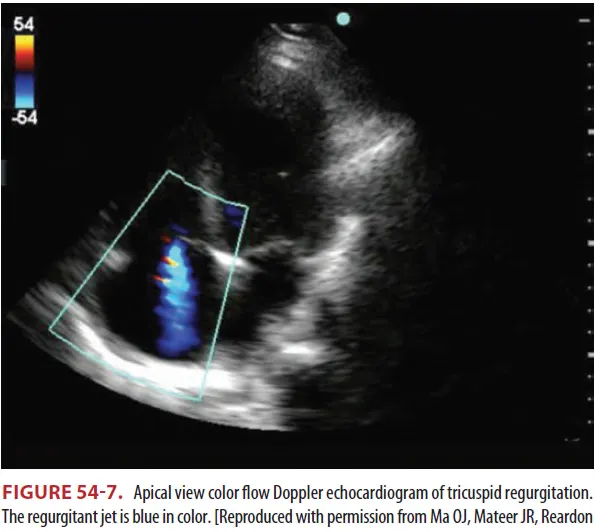

(1) Pathologic tricuspid regurgitation

① 폐동맥 고혈압, 만성 폐쇄성 폐질환, 폐동맥 혈전증, 심방 중격 결손 같은 우심실 압력의 증가

상황에서 발생

(1) 심초음파 : 진단적 Tool, 경식도 초음파가 민감도 더 높다.